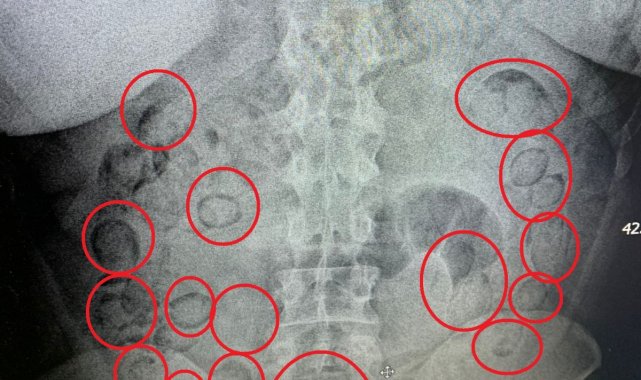

Aksaray'da narkotik ekiplerince düzenlenen operasyonda yakalanan İran uyruklu uyuşturucu tacirinin midesinde 101 parça halinde 433 gram metamfetamin maddesi ele geçirildi.

Edinilen bilgiye göre, İl Emniyet Müdürlüğü Narkotik Suçlarla Mücadele Şubesi ekipleri, yaptığı analiz çalışmasında İran'ın başkenti Tahran'dan ülkeye uyuşturucu getirileceği bilgisine ulaştı. Bunun üzerine Aksaray Cumhuriyet Başsavcılığı koordinesinde harekete geçen ekipler kimliği belirlenen A.M. (20) isimli İran uyruklu şahsı teknik ve fiziki takibe aldı. Narkotik ekipleri şahsın uçakla Ankara'ya geleceği bilgisi üzerine harekete geçti. Ekipler Ankara'da uçaktan inen şahsı takibe aldı. Ankara'dan otobüse binen uyuşturucu taciri otobüsle Aksaray'a geldi. Aksaray'da E-90 karayolunda şahsın otobüsten inmesi üzerine operasyon için düğmeye basan ekipler şahsı kıskıvrak yakalayarak gözaltına aldı. Yapılan kontrollerin ardından uyuşturucuları midesine yutarak muhafaza ettiği düşünülen şahıs Aksaray Eğitim ve Araştırma Hastanesine götürülerek iç beden muayenesinden geçirildi. Tomografisi çekilen şahsın midesinde vücut dışı parçaların olduğu tespit edildi. Hastanede doktor kontrolünde ilaç içirilen İran uyruklu tacir bir süre sonra polis kontrolünde büyük tuvaletini yaparken, şahsın midesinden prezervatife sarılmış 101 küçük paket çıktı. Paketlerin içini açan polis, toplam 433 gram metamfetamin maddesi ele geçirdi. Uyuşturucu maddelere el konulurken, uyuşturucu taciri emniyetteki işlemlerinin ardından sevk edildiği adli makamlarca tutuklanarak cezaevine gönderildi.